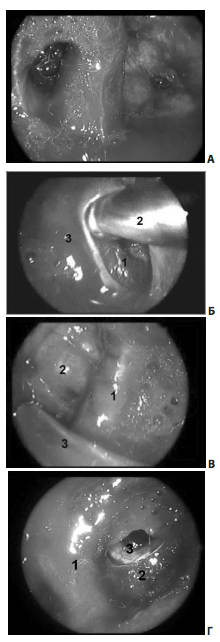

Методика эндоскопического транссфеноидального удаления аденом гипофиза

Использование эндоскопов с различными углами зрения (0 °, 30 °, 45 °, 70 °) дает возможность широкой визуализации не только эндо-, но и экстраселлярных пространств в условиях хорошей освещенности операционного поля, что особенно важно и полезно при манипуляциях в латероселлярном пространстве.

Удаление опухоли из полости кавернозного синуса производится под непосредственным визуальным контролем эндоскопов с углами поля зрения от 0 ° до 70 ° с использованием различных загнутых отсосов и кюреток через дефекты в медиальной стенке кавернозного синуса.

Рис. 7. Удаление опухоли из правого кавернозного синуса (45º эндоскоп): А — синими стрелками показана возможность осуществления манипуляций с обеих сторон сонной артерии; Б Б — удаление опухоли из правого кавернозного синуса (45º эндоскоп): 1 — правая ВСА; 2 — отсос; 3 — медиальная стенка правого кавернозного синуса; В В — удаление опухоли из левого кавернозного синуса (45º эндоскоп): 1 — левая ВСА; 2 — оболочка верхних отделов латероселлярного узла опухоли; 3 — отсос; Г Г — полость правого кавернозного синуса. Доступ через медиальную стенку синуса: 1 — интракавернозный сегмент правой ВСА; 2 — полость кавернозного синуса медиальнее правой ВСА; 3 — через дефект в капсуле виден правый глазодвигательный нерв